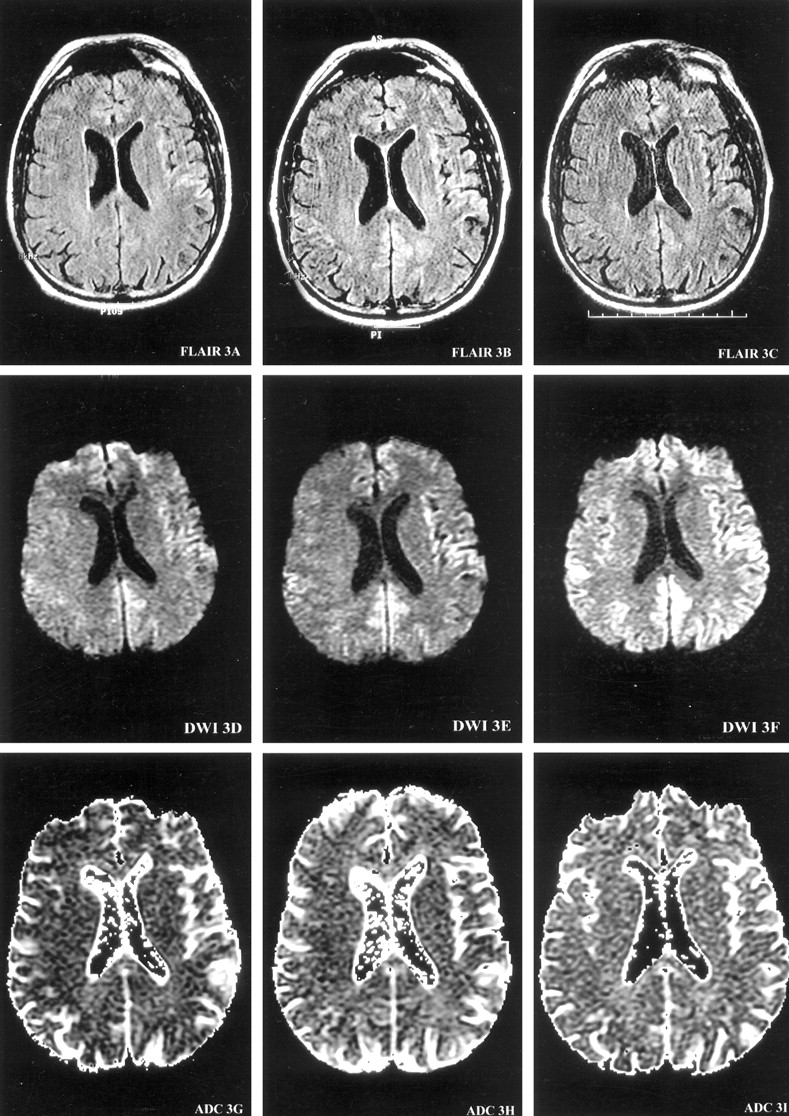

MR imaging of the brain with a DW sequence (9999/98.8 [TR/TE], 5-mm-thick sections, diffusion gradient strength 1000 s/mm2) was performed at 4, 5.5, and 6 months after the onset of symptoms (Fig 1). T1-weighted (566/11.3, 2-ms echo train length [ETL], T2-weighted (4000/102, 16-ms ETL), gadolinium-enhanced T1-weighted (566/11.3, 2-ms ETL), and gradient-echo (750/35) images were consistently normal. At 4 months from onset, DW images demonstrated increased signal intensity in the right temporal cortex in a gyriform pattern. At 5.5 months from onset, the areas of hyperintense signal on DW images involved more cortical gyri and extended to the left temporoparietal cortex. At 6 months from onset, DW images showed a ribbon-like area of hyperintensity involving the right temporoparietal occipital cortex, as well as the left parietal and frontotemporal cortex extending into the parafalcine occipital region (Fig 1). Qualitative apparent diffusion coefficient (ADC) mapping of these regions revealed a decreased signal intensity indicating the presence of restricted diffusion. FLAIR images (10,002/174/2200 [TR/TE/TI]) at 6 months showed subtle hyperintense signal in the left frontotemporal region, corresponding to the observed DW imaging findings (Fig 1). MR proton spectroscopy was performed at 6 months from symptom onset and revealed a slightly decreased ratio of the peaks for N-acetylaspartate to creatine (1.46–1.56 [normal >1.8]) measured in the parafalcine occipital and left frontal cortical regions.

Serial MR images demonstrate the evolution of ribbon-like cortical signal intensity abnormalities. MR images are presented at each of three brain axial levels (1–3), at each of three time points from the onset of symptoms (left columns, 4 months; middle columns, 5.5 months; right columns, 6 months) for FLAIR (top row), DW imaging (middle row), and ADC (bottom row) studies. At 4 months from onset of symptoms, DW images demonstrate gyriform increased signal intensity predominantly in the right temporal cortex (DWI1D) with decreased ADC signal intensity consistent with restricted diffusion (ADC1G). At 5.5 months from onset, the hyperintense signals on DW images involve more cortical gyri, extending into the left temporoparietal cortex (DWI3E). At 6 months from onset, DW images (DWI1F, DWI2F, and DWI3F) show ribbon-like areas of hyperintensity involving the right temporoparietooccipital cortex, as well as the left frontotempoparietal cortex, extending into the parafalcine occipital region.

Images on this page were obtained at level 1.

(continued) Images on this page were obtained at level 2.

(continued) Images on this page were obtained at level 3.